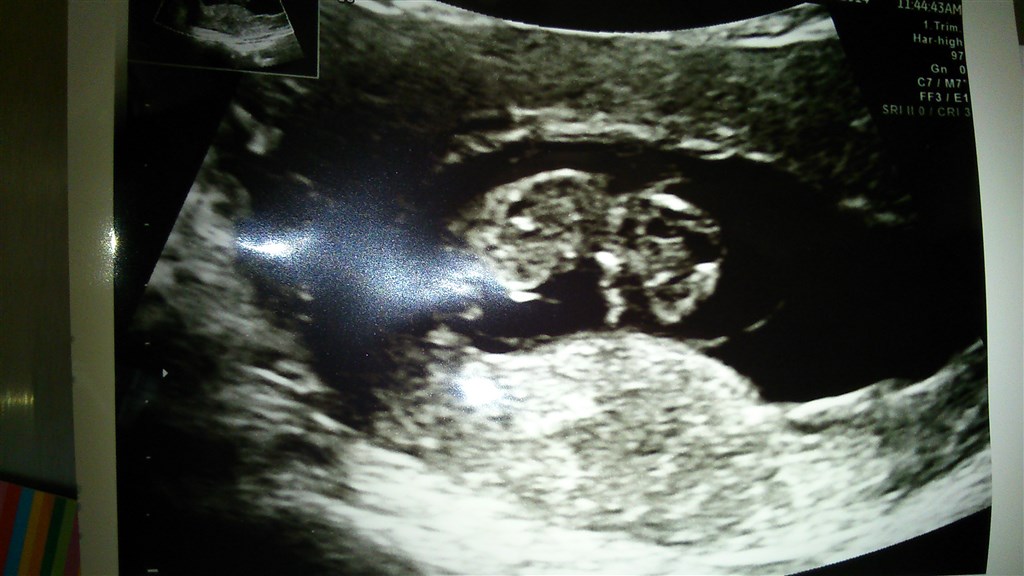

Ikke for at tage modet fra dig, det kan jo godt være at det bliver til noget.. Men jeg har også været i behandling og fik dette billede i uge 7. Fosteret målte her omkring 7-10 mm mener jeg. (Det runde er blommesækken)

Vedhæftede fotos (klik for at se i fuld størrelse)

Anmeld